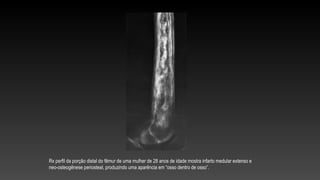

Rx perfil da porção distal do fêmur de uma mulher de 28 anos de idade mostra infarto medular extenso e

neo-osteogênese periosteal, produzindo uma aparência em “osso dentro de osso”.